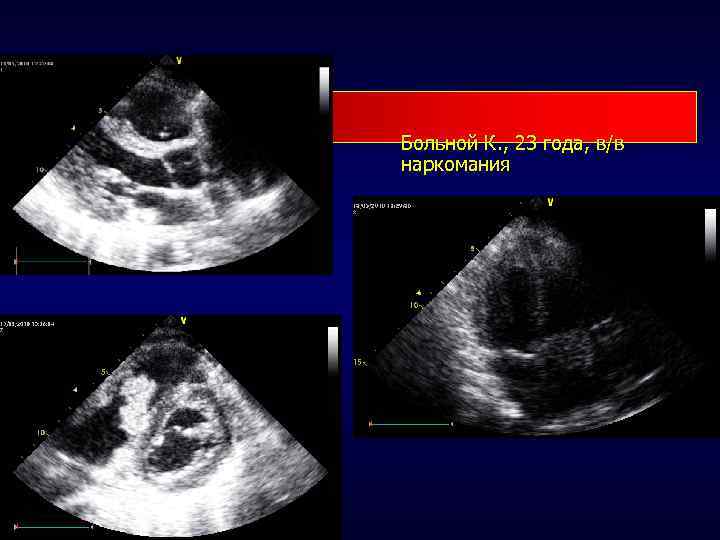

Больной К. , 23 года, в/в наркомания

Вегетации